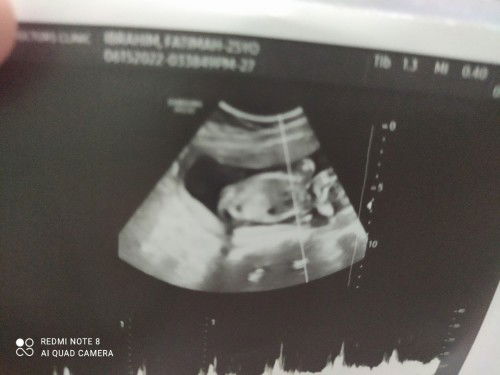

Grade 3 placenta at 35 weeks only

So please pasani nmn sinong nakaranas ng grade 3 placenta at 35 weeks tas 2040 grams lang baby ko, Super risk po ba

Maliit Ang baby ko ng 3 weeks sa exact na edad nya 🥺

Sinong nanganak na dto na maliit ung baby sa edad nya.. 35 and 6 days nako pero 32 and 6 days palang laki Niya . September 27 nag pa ultrasound ako 32 weeks sya then October 18 nag pag ultrasound ako ulit 32 and 6 days lang Sya 🥺 Almost 4 weeks ng lumipas pero 32 weeks prin